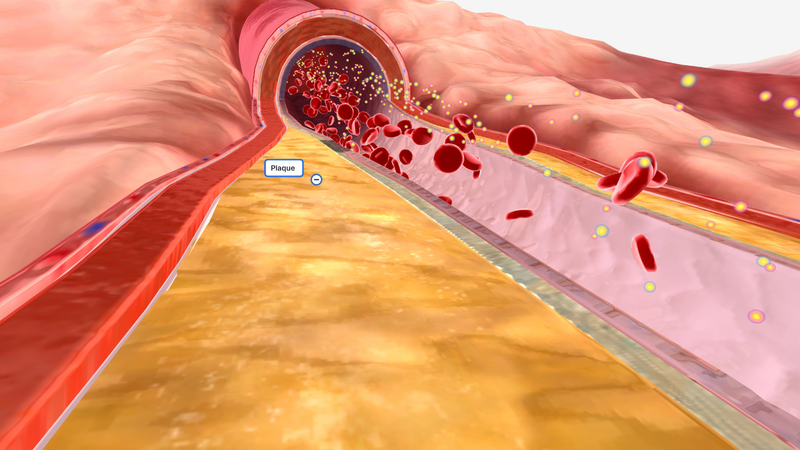

Mỡ màng ngoài tim không phải là một khái niệm xa lạ trong lĩnh vực y học, nhưng chưa bao giờ chúng ta có thể đánh giá chính xác thành phần của nó cho đến nay. Mỡ này có thể là một yếu tố bảo vệ tự nhiên, giúp tim hoạt động hiệu quả trong cơ thể. Tuy nhiên, ở những người mắc bệnh béo phì hoặc có các yếu tố nguy cơ bệnh tim như huyết áp cao, tiểu đường, thói quen hút thuốc và chế độ ăn uống kém, mỡ quanh tim có thể tích tụ quá mức và gây viêm, dẫn đến sự thay đổi cấu trúc của nó theo hướng có hại. Nếu không được kiểm soát, mỡ này có thể giải phóng các chất có hại trực tiếp vào cơ tim, gây ra các vấn đề nghiêm trọng như nhồi máu cơ tim và suy tim.

Phương pháp MRI mà các nhà khoa học UVA đang phát triển giúp phân tích không chỉ lượng mỡ mà còn cả thành phần của nó, từ đó có thể phát hiện sớm nguy cơ mắc bệnh tim ngay cả khi chưa có triệu chứng. Đặc biệt, MRI có thể giúp đánh giá các loại axit béo bão hòa, axit béo đơn không bão hòa và axit béo đa không bão hòa – những thành phần thường có trong chế độ ăn uống của chúng ta. Điều này giúp bác sĩ dự đoán các vấn đề tim mạch có thể xảy ra trước khi chúng trở thành triệu chứng rõ rệt.

Sau những thử nghiệm ban đầu, nhóm nghiên cứu UVA đã tiến hành thử nghiệm công nghệ MRI mới này trên một số bệnh nhân. Kết quả cho thấy, ở những bệnh nhân béo phì và từng bị nhồi máu cơ tim, mỡ quanh tim chứa một lượng lớn axit béo bão hòa. Điều này gợi ý rằng phương pháp MRI mới có thể trở thành một công cụ hữu ích trong việc phát hiện các bệnh nhân có nguy cơ cao và dự đoán kết quả điều trị của họ.